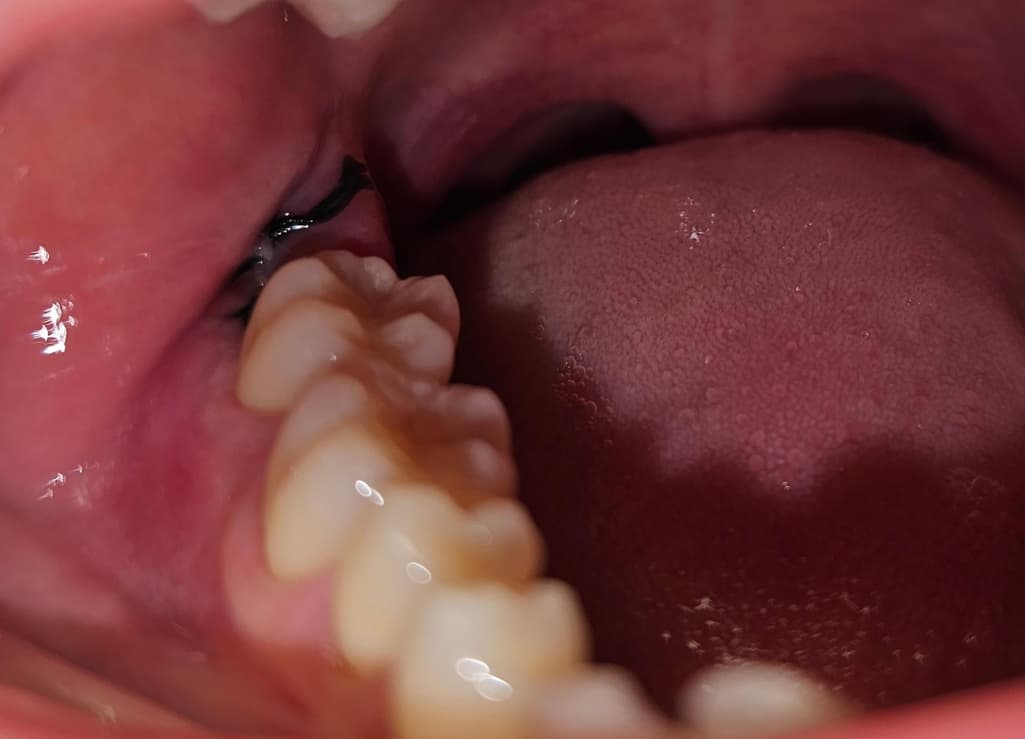

사랑니 발치 5일차, 실밥 풀린건가요?

염증이 생긴것처럼 불편하고 만지면 약간 아프기도 합니다. 특히 윗니를 양치하다 칫솔로 건드리면 많이 아픕니다.

실이 풀린건지 씹히기도 하는데 실밥이 풀린건가요?

사진으로는 실밥이 보이기 때문에 풀린것으로 보이지는 않습니다. 사랑니를 발치하고 나면 발치한 부위가 자극되지 않도록 하는것이 좋습니다.